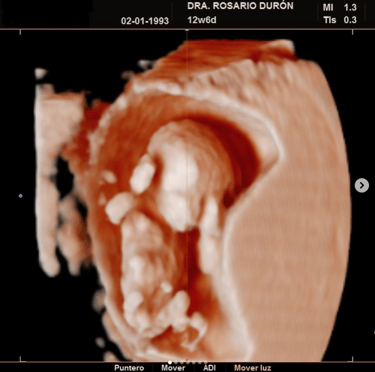

Diagnóstico prenatal avanzado

Mediante técnicas como la ecografía genética, la medición de la translucencia nucal y la cardiotocografía para detectar anomalías.